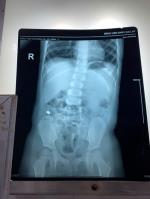

Bệnh sởi là bệnh lây truyền cấp tính qua đường hô hấp, do virus thuộc giống Morbillivirus của họ Paramyxoviridae gây nên. Đặc điểm để nhận biết bệnh sởi ở trẻ em là sốt, viêm long đường hô hấp và tiêu hóa, viêm kết mạc mắt, nổi các vết phát

ban dát đỏ lan theo thứ tự từ mặt đến tay chân và cả cơ thể.

Sự nguy hiểm của bệnh sởi chính là những biến chứng do bệnh gây ra. Trẻ em là đối tượng có nguy cơ nhiễm bệnh rất cao, nhất là khả năng bị những biến chứng nặng nề của bệnh